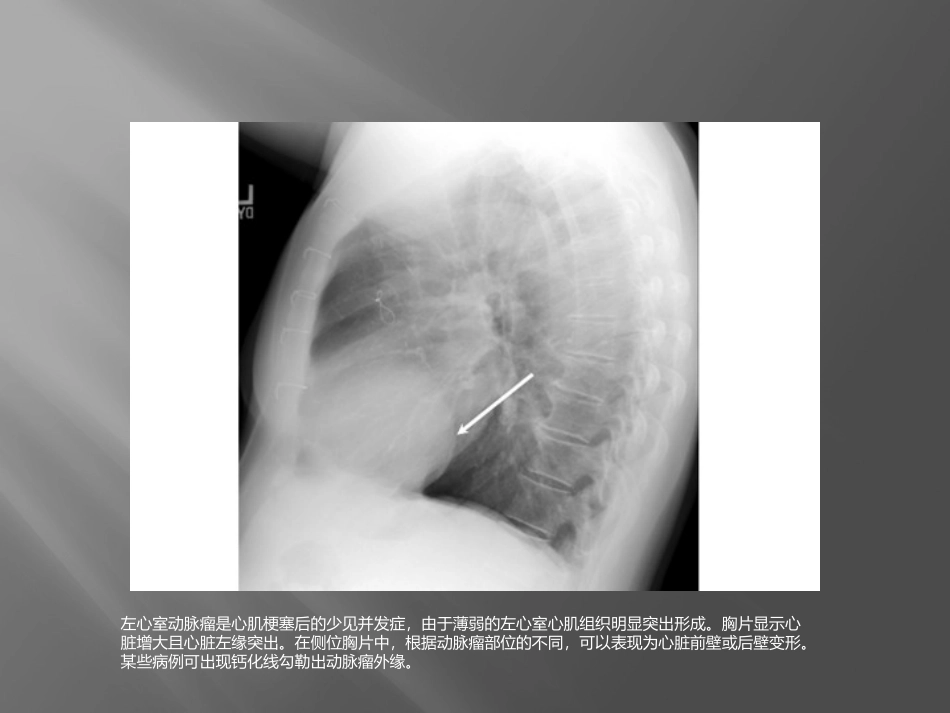

急诊常见X线表现左心室动脉瘤是心肌梗塞后的少见并发症,由于薄弱的左心室心肌组织明显突出形成。胸片显示心脏增大且心脏左缘突出。在侧位胸片中,根据动脉瘤部位的不同,可以表现为心脏前壁或后壁变形。某些病例可出现钙化线勾勒出动脉瘤外缘。气液胸指胸膜腔内同时含有气体和液体。气液胸可见于食道破裂(如图所示)、创伤、产气微生物感染、支气管胸膜瘘或手术造成的医源性损伤。直立位胸片通常显示贯穿一侧胸腔的气液平。仅当胸膜腔内同时存在气体和液体时才能出现气液平。置气管插管后,最初通过双肺听诊以及CO2监测确定插管位置,但是常规需要拍摄胸片进行确认。气管插管内嵌有不透X光的线条,以便确认位置。插管尖端应当在隆突(折线)上2-6cm(箭头)。插管尖端位于这一位置时,可以在颈部屈曲或伸展时仍保证通气充分。如果插管位置过深,则可能造成选择性单肺插管,导致对侧肺完全不张。肺不张指因肺泡塌陷导致的部分肺或全肺容积减少。肺不张的原因包括肺泡内气体被吸收后造成的阻塞性肺不张,以及由于压迫、表面活性物质缺乏、肺实质形成瘢痕或胸膜脏层和壁层不再接触造成的非阻塞性肺不张。根据受累部位和程度不同,胸片表现存在很大差异。肺叶塌陷可以表现为叶间裂移位,塌陷肺叶部位致密影,以及纵隔向同侧移位,肋间隙变窄,膈肌升高和胸腔容积减少。心脏附近肺叶不张可以使得胸片上心脏边界不清。上图所示右中叶不张,并造成心脏右缘边界不清肺栓塞指肺动脉血流受阻。肺栓塞的临床表现各异,因此准确诊断非常困难。尽管CT血管造影以及通气灌注扫描通常用于确诊肺动脉栓塞,但胸片也可能存在多种征象。Westermark征指肺血管扩张且突然中断。Hampton驼峰为肺梗死和不张引起的周边肺组织的楔形实变(如箭头所示)。胸片还可见少量胸腔积液及膈肌抬高。值得注意的是,多数情况下肺栓塞患者胸片正常。连枷胸为至少3根肋骨2处或多处骨折造成胸壁节段的矛盾运动。在吸气相,由于受到胸腔内负压的影响,受累节段回缩。连枷胸通常见于胸部严重钝性创伤患者。根据胸片评估肋骨骨折可能非常困难,有时需要拍摄多角度斜位片,并密切关注细节。上图为胸片的放大影像,显示由箭头所示肋骨骨折造成的连枷胸。如果怀疑骨折但未得到胸片确诊,可能需要进行CT扫描。吸入性肺炎是口咽部细菌或胃内容物吸入肺内导致的感染。吸入性肺炎与吸入性肺泡炎不同,后者由吸入物的直接化学损伤导致。胸片典型表现为双侧中下肺区域的致密影(如图所示)。急性期可出现一过性浸润影或肺叶实变,而慢性误吸可表现为团块影。充血性心力衰竭是一种临床综合征,指患者心脏泵出的血不能满足组织代谢需要。胸片可出现多种典型的表现。其一为心脏增大,后前位胸片显示心胸比例增加超过50%(白线)。肺组织周边可出现KerleyB线,为小叶间隔增厚的结果。胸水增多可使肋膈角变钝(红色箭头)或导致大量胸腔积液。肺水肿可以造成双侧肺纹理增加,并呈肺门周围或蝙蝠翅状分布。肺毛细血管压增加导致上叶血管直径与下叶血管相等或更粗,即头侧化(cephalization)。膈疝即膈肌缺损导致腹腔内容物进入胸腔内。多数情况下膈肌缺损发生在左侧,其原因可能与左侧膈肌较为薄弱或肝脏的保护作用有关。胸片可见双侧膈肌不对称,或膈肌水平改变(箭头)。胸腔内出现充气气管或鼻胃管有助于确诊。腹腔实质脏器一旦疝入胸腔,则表现为蘑菇形均质致密影。膈肌麻痹或肺减容手术后患者可能误诊。胸主动脉瘤指超过正常升主动脉、主动脉弓或降主动脉直径50%的瘤样扩张,其中以降主动脉瘤最为常见。胸片最常见表现为纵隔影增宽(白色箭头),主动脉球增大,气管移位(红色箭头)。其他影像学表现包括主动脉双影(分别代表真腔和假腔),沿主动脉走行出现局灶性突出,以及降主动脉和升主动脉直径不一致。急性呼吸窘迫综合征定义为急性起病,PaO2/FIO2≤200mmHg,胸片双侧浸润影,以及肺动脉楔压≤18mmHg或没有左房压升高的临床表现。胸片上最常见的表现为双侧非对称性实变伴支气管气像(如箭头所示),主要位于周边。间隔线及胸腔积液并不常见。渗出期的早期表现包括双侧实变,并可掩盖肺血管纹理。这些病变可以演变为更弥漫的非...